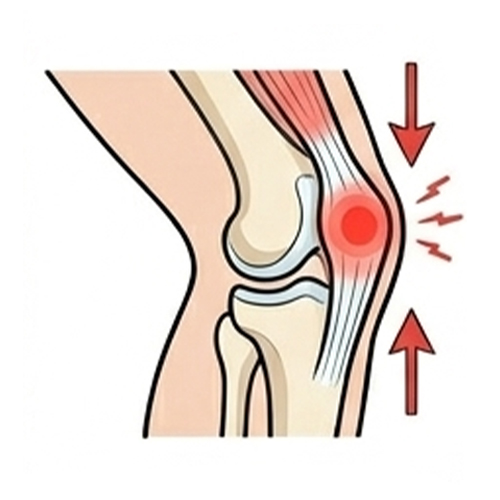

Patellofemoral Pain Syndrome (Runner’s Knee)

Pain around or behind the kneecap, typically from alignment or muscle imbalance.